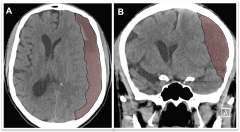

Figure 1

Figure 1. A) Axial view of a brain CT scan demonstrating a chronic subdural hematoma collection below the skull (the skull is bright white) shifting the brain (brain surface is marked with the yellow line) to the other side. B) Coronal view of the same patient demonstrating the chronic subdural hematoma occupying the subdural space and shifting the brain to the other side (brain surface marked with yellow line).